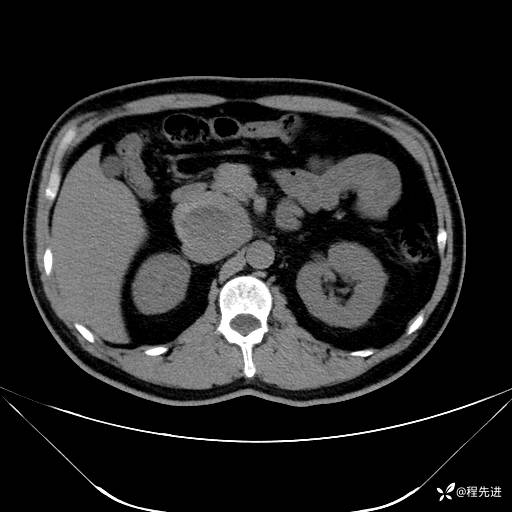

【腹盆】特别精彩病例|发现腹膜后肿物1月余

主诉:发现腹膜后肿物1月余

现病史:患者1月余前查体,行超声检查提示:后腹膜囊实性肿块;慢性胆囊炎伴胆囊内结石;无腹痛腹胀,不伴腹泻发热等;偶感腰背部酸痛。

CT平扫+增强: